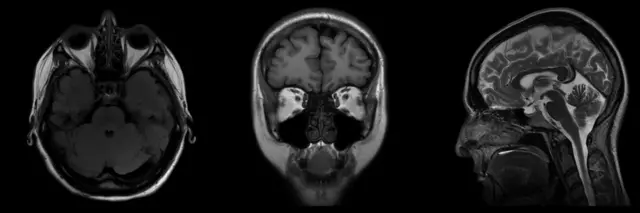

हे सिग्नल्स रेडिओ फ्रिक्वेन्सी कॉईल्स (Radio Frequency Coils) नावाच्या विशेष उपकरणाद्वारे टिपले जातात. कॉम्प्युटर या सिग्नल्सवर प्रक्रिया करून त्यातून शरीराच्या अंतर्गत रचनेचं तपशीलवार चित्र तयार करतो.

या पद्धतीमुळे मेंदू, स्नायू, हृदय आणि सॉफ्ट टिश्यूज् असणाऱ्या शरीराच्या आतल्या इतर अवयवाचं स्पष्ट चित्र मिळू शकतं. म्हणूनच याच्याशी संबंधित रोगांच्या निदानासाठी एमआरआय चाचणी करणं महत्त्वाचं ठरतं.

- ट्यूमर, स्ट्रोक, मल्टिपल स्क्लेरोसिस आणि पाठीच्या मणक्याच्या दुखापतींच्या निदानासाठी मेंदू आणि पाठीच्या कण्याचा एमआरआय केला जातो.

पण एमआरआय मशीन्स 3डी इमेजही तयार करू शकतात आणि ती वेगवेगळ्या कोनांमधून, बाजूंनी पाहता येऊ शकतात.